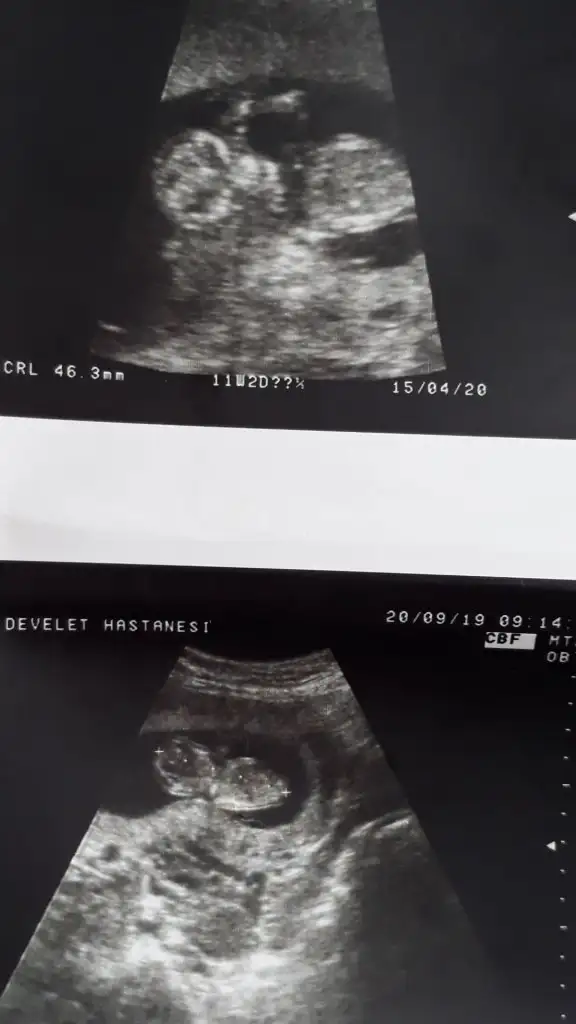

Kizlar benim bebegim erkek. Tum ultrasonlarini attim. Sirasi biraz karisti sanirim. Siz bakip tum teorilere gore karar verin. Nub dan baskasi dogru degil sanki he?

Tesekkur ederim. Evet skull teorisi var bir de. Ona gore de kiz olmasi gerekiyordu ki zaten kafa yapisi ablasinin ultrason goruntusu ile aynı. O haftalarda cok kafa yormustum bunlara. Diyecegim o ki rahat olup beklemek gerek. Bu arada çin ve rus takvimi de kiz:)

Bende inanmiyorum yani zaten sallasanda %50 dogruluk payi var :) denk geliyor sadece bence.

Nub teorisinde erkek yorumlamıştım usgnizi